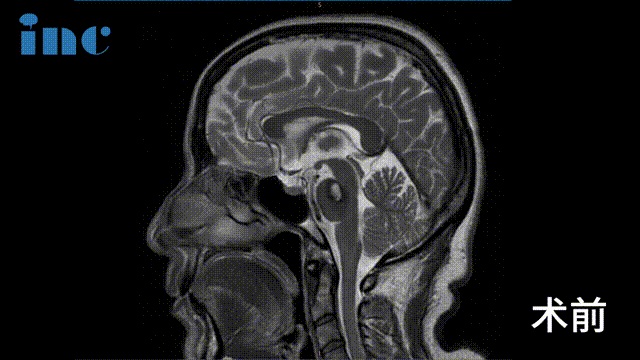

▼术前及术后1天影像对比

2023年9月28日,巴教授于苏州大学附属独墅湖医院为金女士顺利手术,巴教授成功为金女士取出了这颗脑干位置的不定时炸弹,无任何新发神经功能损伤,同时巴教授也成功进行了面神经解压术,解决了金女士面肌痉挛的问题。

影像对比提示金女士的海绵状血管瘤增大,出血量逐渐增多

术前影像:面神经受压迫